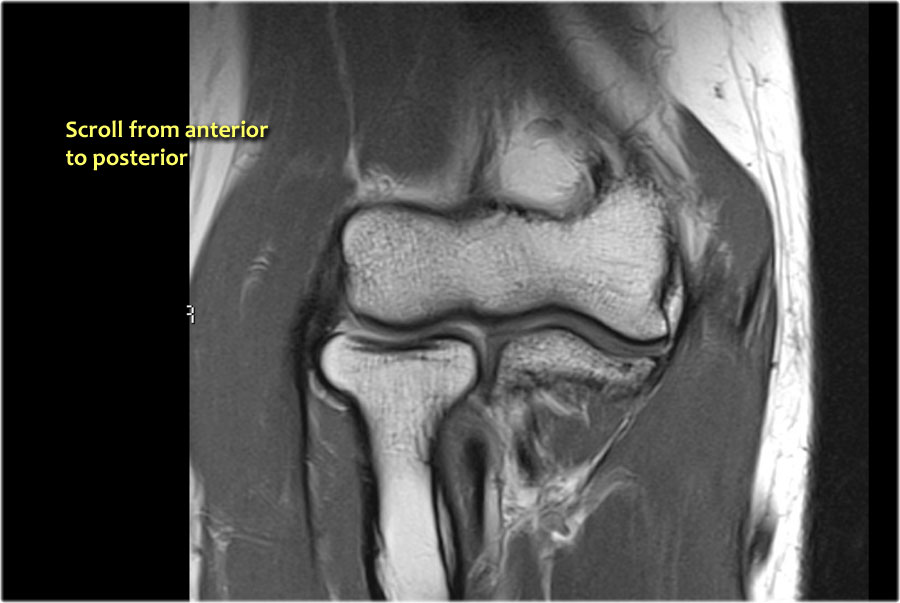

Scroll through these images.

You can also enlarge them.

Common Extensor Tendon

Gân duỗi chung xuất phát từ mỏm trên lồi cầu ngoài.

Trên ảnh T1W, gân phải có tín hiệu thấp (mũi tên vàng).